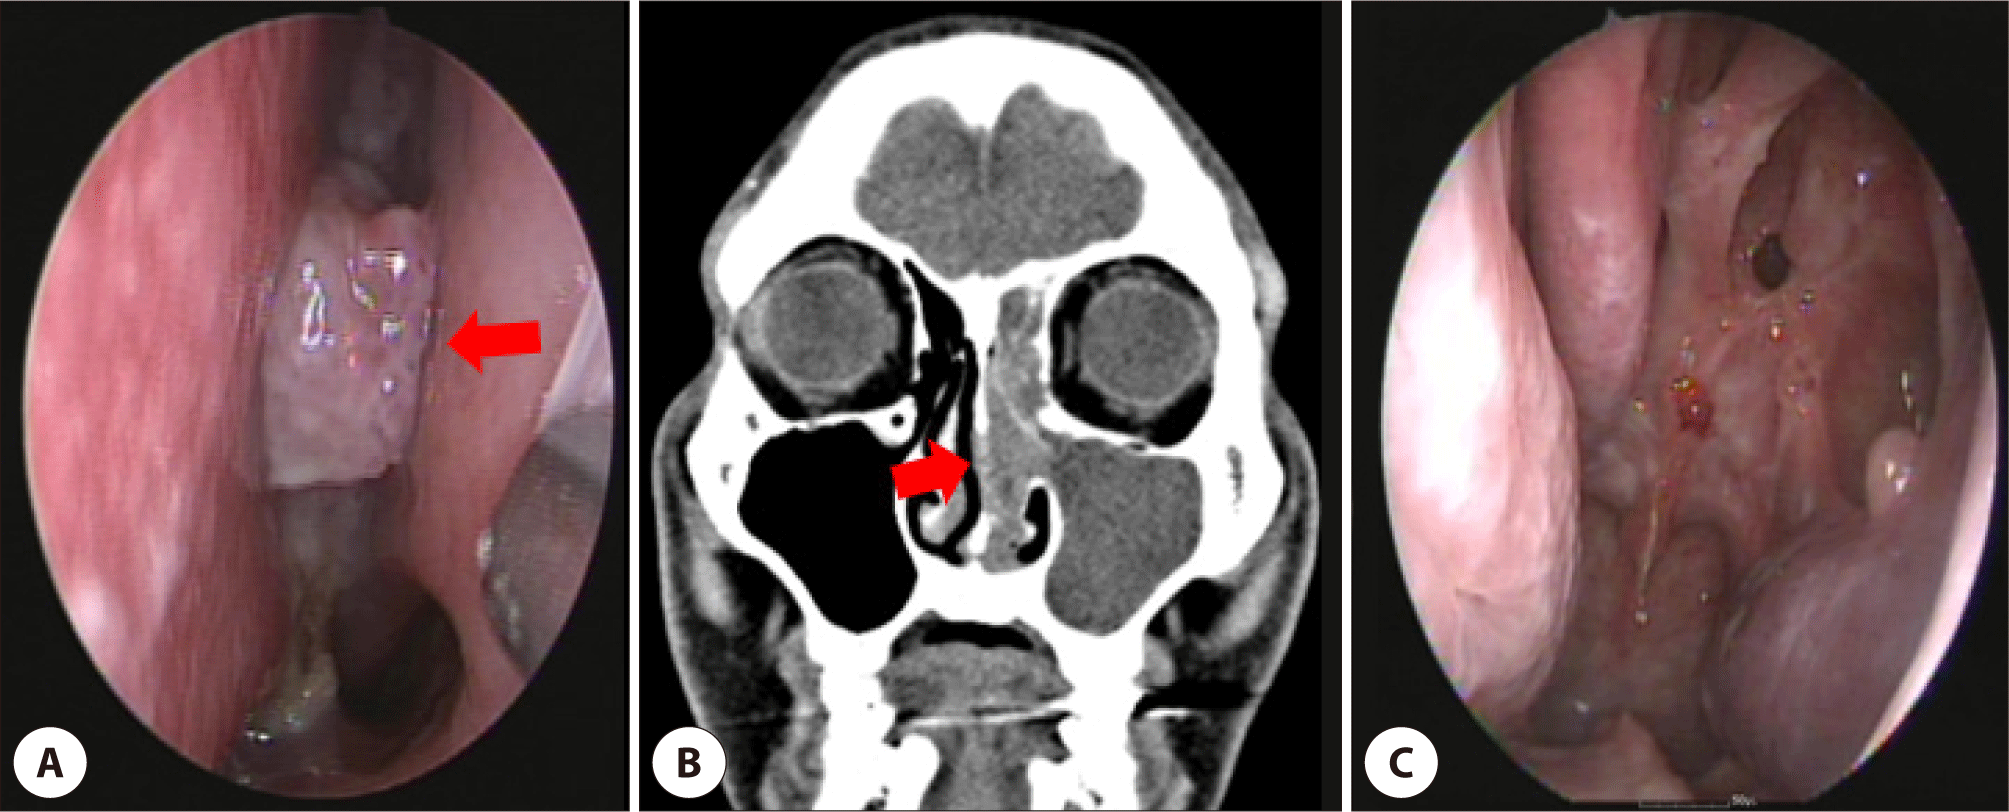

Five years later, he presented progressive bilateral nasal congestion and epistaxis. On nasal endoscopy, a posterior nasal septal mass of about 1.0 cm was observed (Fig. 2A). On computed tomography (CT) of the nasal sinuses, a round mass measuring 1.0×0.6 cm with soft tissue opacification in the nasal septum and left nasal cavity, and haziness of the left frontal sinus was observed (Fig. 2B). On magnetic resonance imaging (MRI), the tumor revealed an irregular margin with surrounding tissues and bone destruction of the posterior nasal septum. Positron emission tomography revealed a hypermetabolic lesion extending to the left ethmoid sinus. The mass was histopathologically diagnosed as SCC punch biopsy. Endoscopic nasal septectomy and left anterior middle turbinectomy were performed, and histopathology confirmed invasive SCC involving the posterior nasal septum and left middle turbinate with negative resection margins (Fig. 2C). No adjuvant radiotherapy was administered, and the patient remained disease-free for 2 years.

Fig. 2. (A) Preoperative endoscopy shows a septal mass of about 1.0 cm long, fungating to the left nasal cavity (arrow). (B) Coronal view of non-enhanced face CT shows the 1.0x0.6 cm round mass with soft tissue density (arrow) and sinusitis of the left maxillary, ethmoidal and frontal sinus. (C) Postoperative rhinoscopy shows the removed posterior septum and left medial maxillary wall.